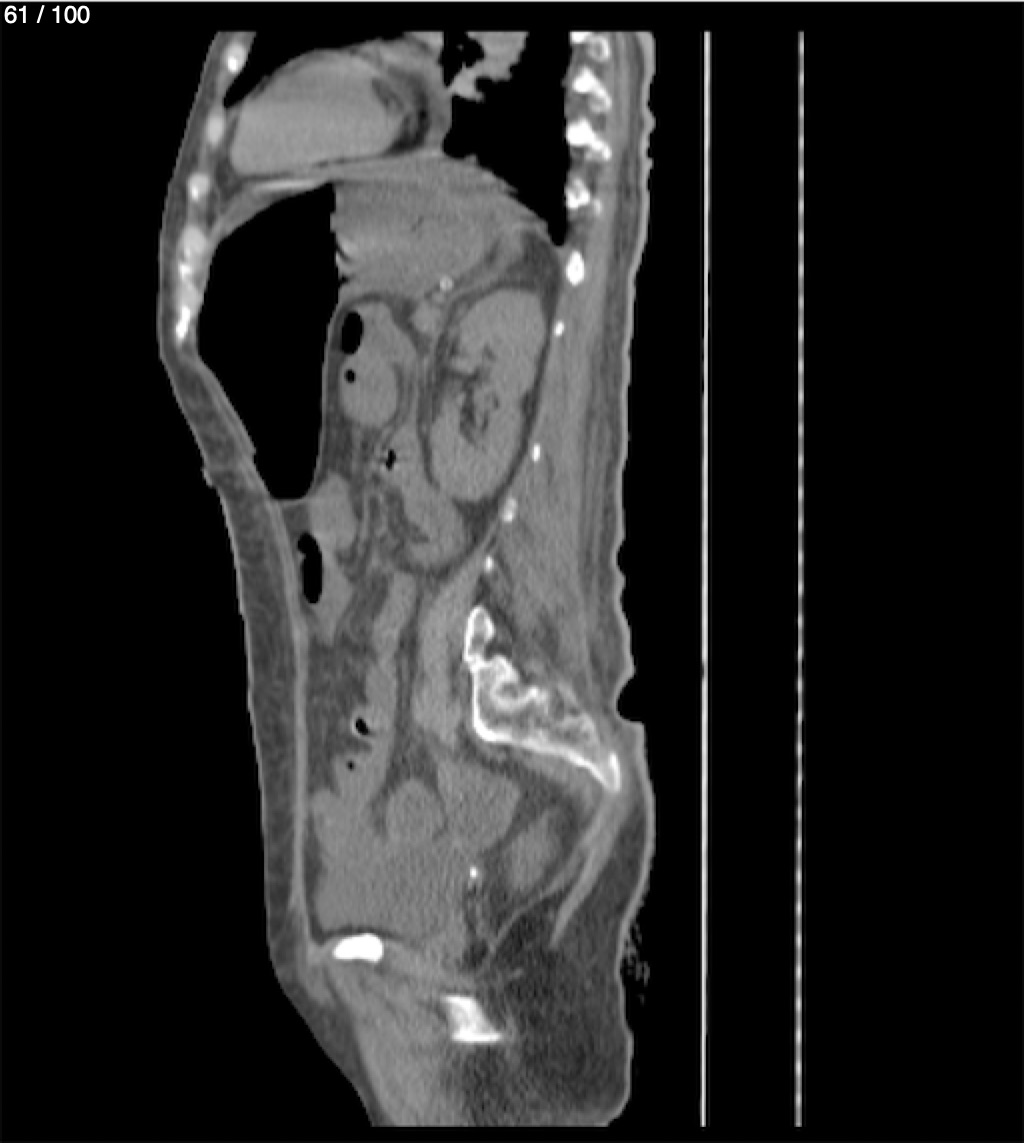

Hilda Geronimo Mendez 60A - T.C Abdomen Simple